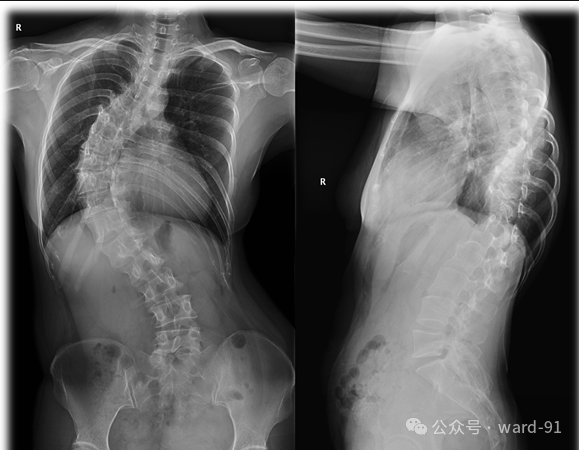

脊柱X线解剖图像